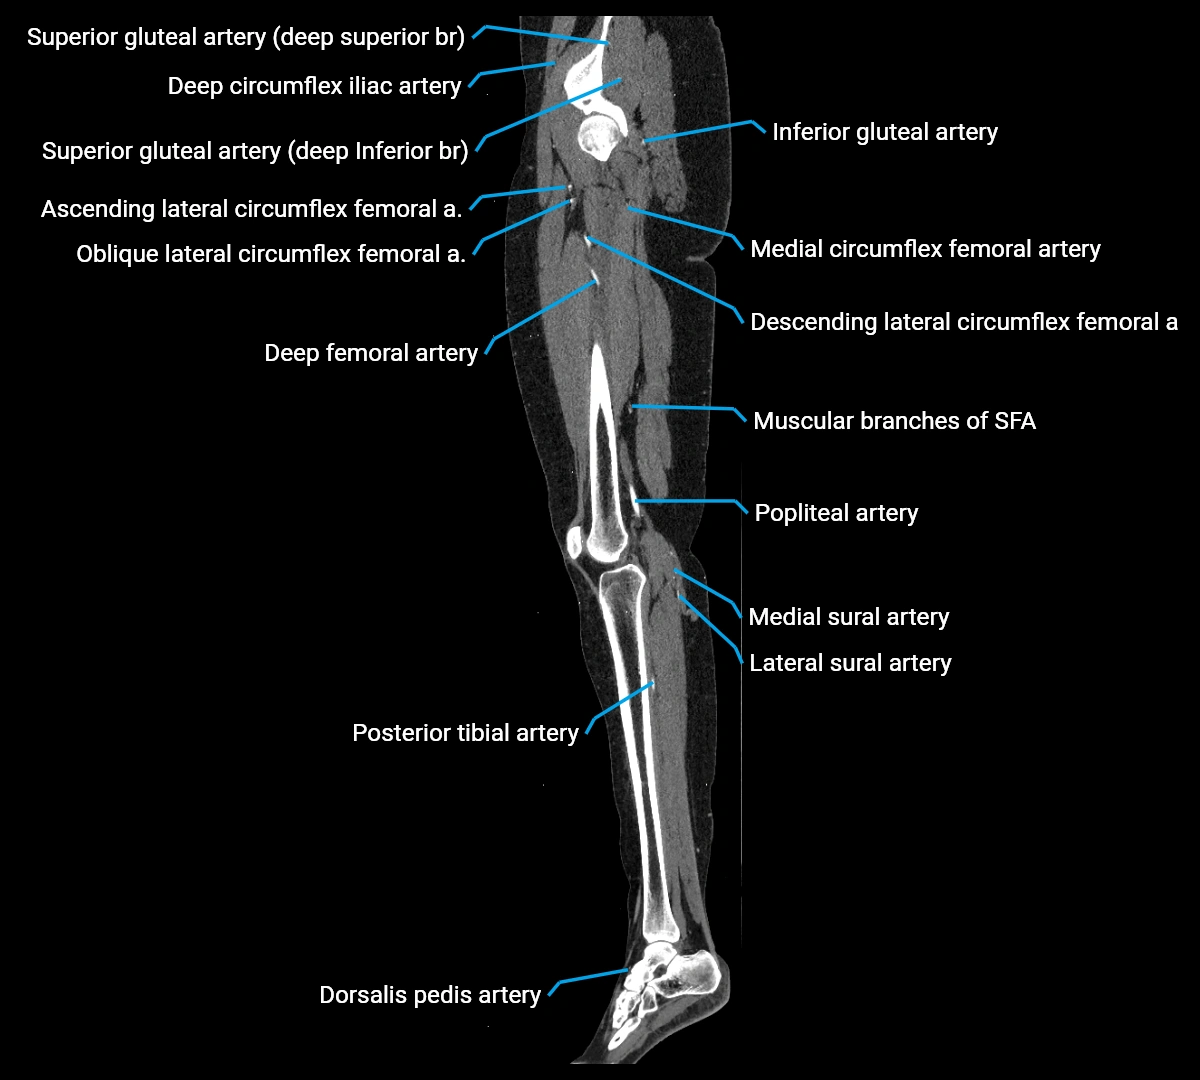

CT images

image

Contrast-enhanced CT (CTA):

• Gold standard for abdominal aortic imaging

• Provides excellent detail of lumen, wall, aneurysm, thrombus, and branch vessels

• Multiplanar and 3D reconstructions help in aneurysm measurement, stent graft planning, and dissection evaluation

• Detects acute rupture, traumatic injury, or occlusion with high sensitivity